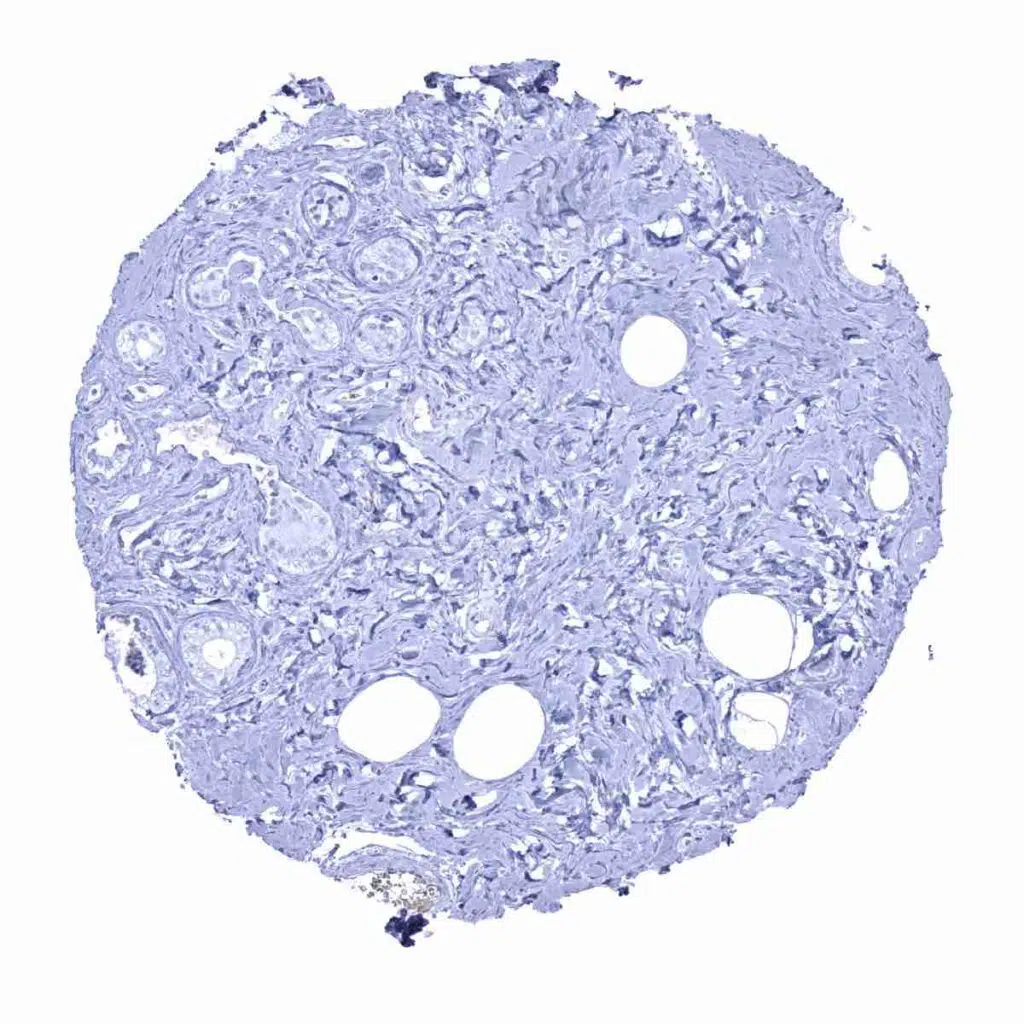

Prostate